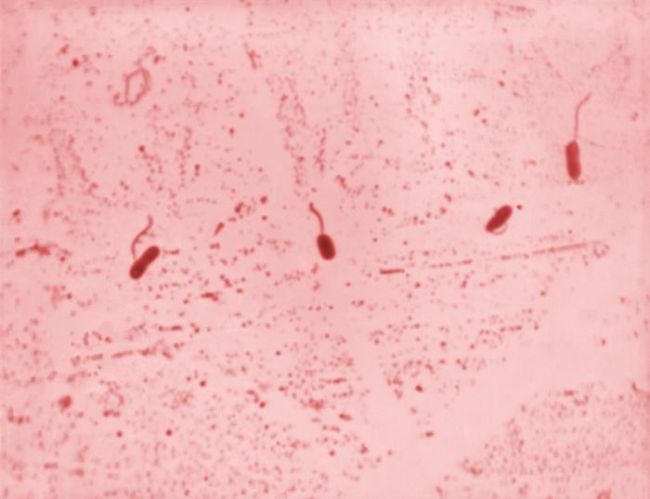

在顯微鏡下弧菌只有一個彎曲,呈弧狀或逗點狀,尾部帶一鞭毛,形態(tài)多樣,包括桿狀、弧狀等。如霍亂弧菌。革蘭氏染色陰性,長0.8~3μm、寬0.5~1.5μm

綜上所述,生物顯微鏡是觀察細菌,包括弧菌,的重要工具,不僅可以了解其形態(tài)和運動特性,還可以結(jié)合其他實驗室檢測方法進行菌種鑒定和疾病診斷,對于霍亂等由弧菌引起的傳染病,顯微鏡觀察是初步診斷的重要手段之一